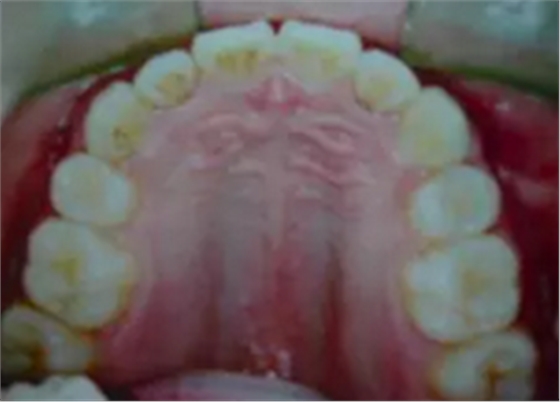

答二、拔牙以后的牙縫在矯治器的作用下,是完全可以關(guān)閉的。

一般來(lái)說(shuō),拔牙以后的牙縫可以被兩個(gè)方面的牙齒移動(dòng)所關(guān)閉,一個(gè)是前面不齊、前突的牙齒向拔牙間隙移動(dòng),占據(jù)部分拔牙間隙,還有就是后面的大牙也可以向關(guān)(拔牙間隙)移動(dòng),這樣就可以關(guān)閉了這個(gè)間隙。